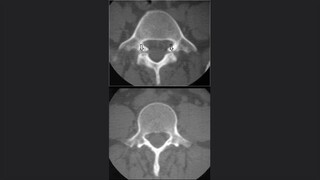

La valoración de la médula

La osteoradiología

La importancia de la tomografía

Generalidades de la fractura